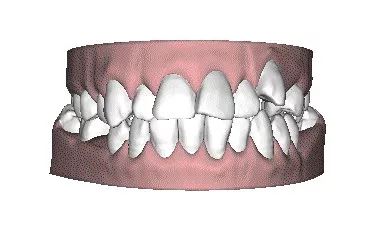

1.牙齿前突(龅牙)

牙齿前突的现象在中国人中算是相当常见的,牙齿前突不仅会造成嘴巴突出,影响美观,还比较容易出现法令纹,看起来有些显老。

2.反颌(地包天)

正常状态下我们咬合牙齿,上牙会比下牙略往前一点,但“地包天”的情况则刚好相反。这样也容易让整个脸型成为人们所说的“猪腰子脸”“月牙脸”,特别影响美观,对牙齿咬合也存在影响。

4.深覆合

咬合过深,指上前牙切缘盖过下前牙牙冠长度1/3以上或下前牙咬合于上前牙舌侧1/3以上者。

因为咬合太深,从侧面看面部下半部分过短以及下巴后缩。深覆合不仅会加重前牙的磨耗,影响牙周组织的健康,还可能诱发颞下颌关节病变等问题。

5.开颌

口腔不良习惯如吐舌、舔牙、伸舌、吸手指等,是常见引起牙齿开合的原因。开合因前牙咬不到一起,非常影响前牙咀嚼,因此开颌常一起伴有肠胃及呼吸道问题。

以上这些问题,都可以通过牙齿矫正来改善,牙齿矫正不仅能让我们收获一口整齐的牙齿、自信的笑容,还能调整咬合关系、面部结构,改善凸嘴、瘪嘴、下巴后缩等一系列面部问题。